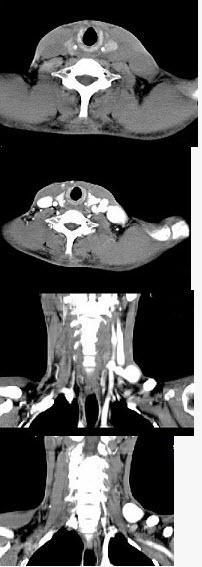

男,46岁,外伤后左下颈搏动性肿块,CT如图所示,最可能的诊断为()。

A、左颈部血管瘤

B、左颈动脉体瘤

C、左颈静脉球瘤

D、左颈总动脉假性动脉瘤

E、左颈部动、静脉畸形

D